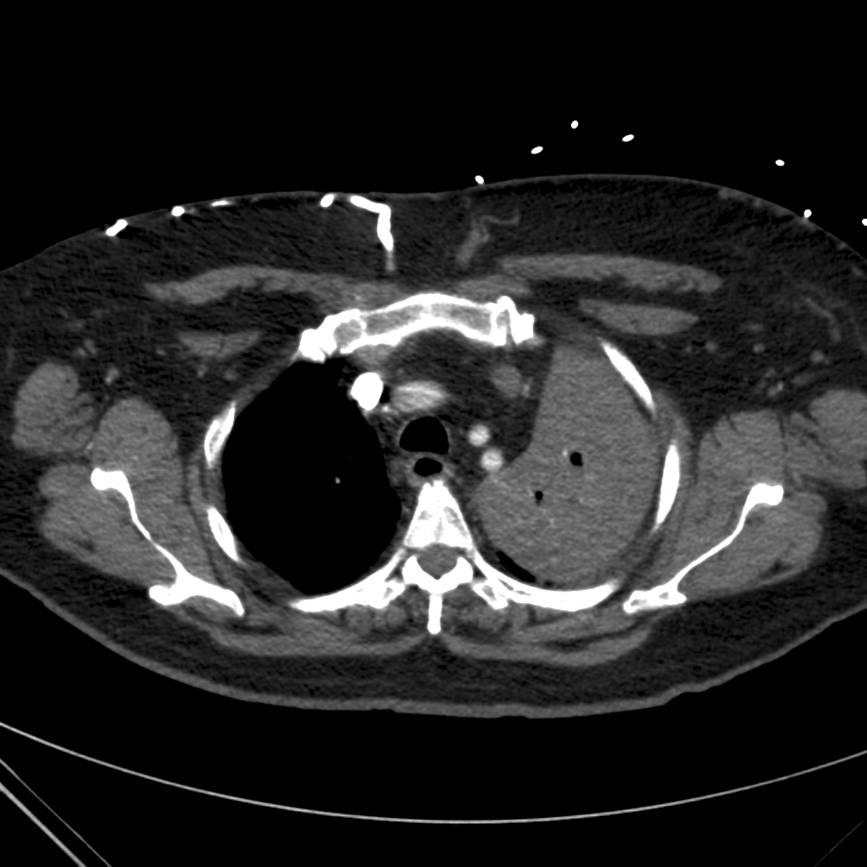

Subsequently the patient underwent computed tomography (CT) of the chest with pulmonary angiography. Two cuts are provided below (Figures 3 and 4).

Figure 4. Computed tomography image of the chest demonstrating left upper lobe (LUL) consolidation with endobronchial lesion in LUL bronchus.